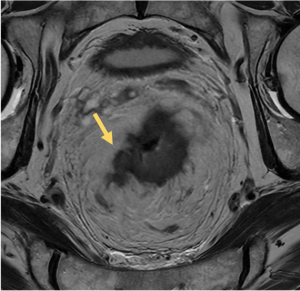

Differences in T2w signal intensity of the rectal wall layers allow accurate assessment of mural invasion and regional spread. The mucosa and muscularis propia appears hypointense while the submucosa is hyperintense.

- T1-T2: Preservation of the hypointense muscularis propia indicates tumor confined to the wall. Differentiation of T1 or T2 is not possible without submucosal edema.

- T3: Tumor extension into the mesorectal fat, beyond muscularis propia. T3 can be subclassified according to the extramural invasion depth: